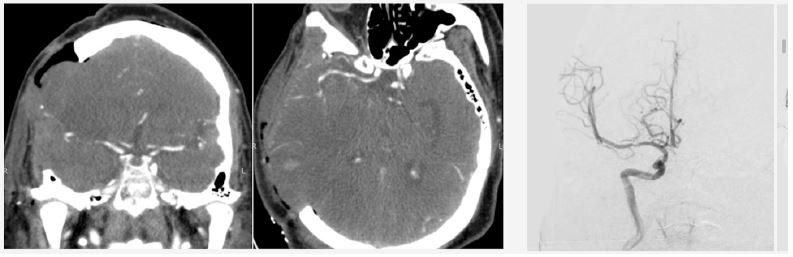

Twenty-four hours post-admission, his neurological status worsened (GCS decreased by 4 points), and a CT scan showed a significant midline shift. A right-sided frontotemporoparietal decompressive craniectomy was performed. Postoperatively, his GCS improved to 14 and motor strength improved to 3/5 on the Lovett scale (Figure 2). A Computed Tomography Angiography (CTA) performed 48 hours after surgery showed restored flow in the M1 and distal branches of the right MCA (Figure 3). A confirmatory cerebral angiogram at two weeks demonstrated patent flow throughout the MCA distribution (Figure 4).

Figure 3: Computed tomography angiography 48 hours after decompressive craniectomy, showing vascular flow in the right MCA territory.

Figure 4: Cerebral angiography 2 weeks later, showing recanalization of the right MCA.